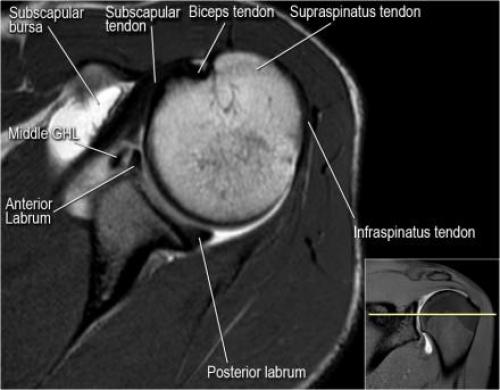

- волокна сухожилия подлопаточной мышцы, создавая бицепитальную борозду, удерживают сухожилие длинной головки двуглавой мышцы. Изучите хрящи.

- уровень средней плече-лопаточной связки и передних отделов суставной губы. Поищите комплекс Буффорда. Изучите хрящи.

- вогнутость заднебокового края головки плечевой кости не следует путать с повреждением Хилл-Сакса, поскольку это нормальная форма для данного уровня. Повреждение Хилл-Сакса визуализируется только на уровне клювовидного отростка. В предних отделах мы сейчас на урвоне 3-6 часов. Здесь визуализируются повреждение Банкарта и его варианты.